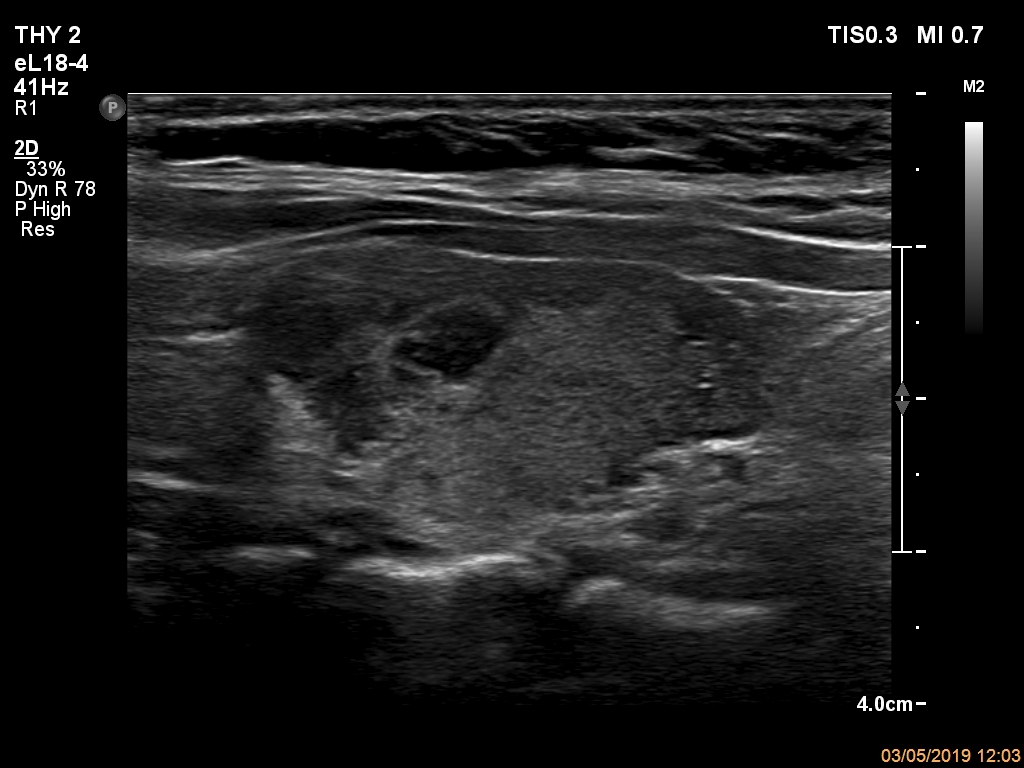

Right lobe, longitudinal scan

Left lobe, longitudinal scan. The most hypoechoic lesion has irregular margins.